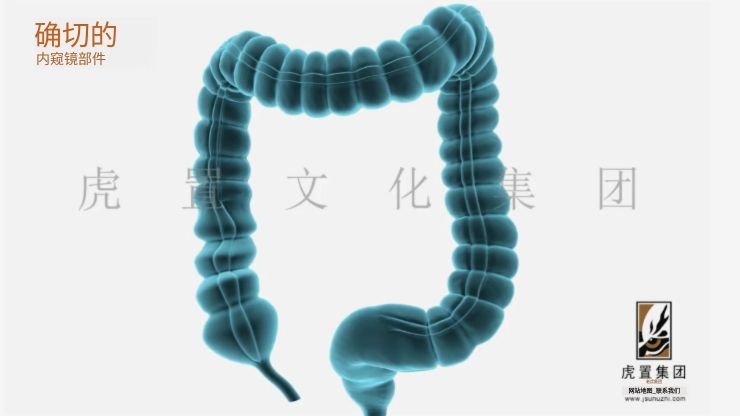

从项目规模来看,不同类型的3D动画制作所需时间差异显著。简单的产品展示动画,比如一个30秒的手机3D展示视频,通常需要2-4周完成。这类项目建模相对简单,动画效果要求不高,渲染时间也较短。中等复杂度的企业宣传片或建筑漫游动画,时长在1-3分钟的话,制作周期一般在4-8周。这类项目需要更精细的模型,更复杂的动画效果,以及更完善的后期处理。而大型影视级动画项目,如动画电影或电视剧集,则可能需要数月甚至数年的制作周期。其制作周期就长达8年,当然这包含了剧本创作等前期工作。

项目复杂度是影响制作周期的另一个关键因素。角色动画的制作周期通常比产品动画长很多,因为需要设计角色模型、骨骼绑定、表情系统等。一个30秒的角色动画可能需要6-8周,而同样时长的产品动画可能只需3-4周。特效的复杂程度也会显著影响制作时间,流体模拟、毛发渲染等高级特效都需要额外的时间投入。此外,场景的复杂程度、是否需要物理模拟等因素都会对制作周期产生重要影响。

制作流程的每个环节都会占用一定时间。前期策划阶段包括创意构思、脚本撰写、分镜设计等,通常需要1-2周。这个阶段看似不直接产出画面,但好的前期规划能大幅提升后续工作效率。3D建模阶段根据复杂度不同需要1-3周,高精度模型可能需要更长时间。材质贴图需要1周左右,灯光设置也需要几天到一周不等。动画制作阶段,简单的产品动画可能只需几天,而复杂的角色动画可能需要数周。渲染环节往往是最耗时的,一帧高质量的渲染可能需要数小时,一个1分钟的项目可能需要数千小时的渲染时间。后期合成包括调色、特效合成等,通常需要1-2周。

虎置集团一直专注于产品动画、卡通动画、影视广告、3D效果图等综合设计服务。拥有北、上、广、深四大数字科技创意中心,国内先进的研发团队和用户体验研究实验室,新锐设计师及软硬件工程师超过100人。20年来,雄厚的技术实力助力虎置打造数字产品项目超过100个,累积设计数字项目500个,行业标杆性项目愈十个。